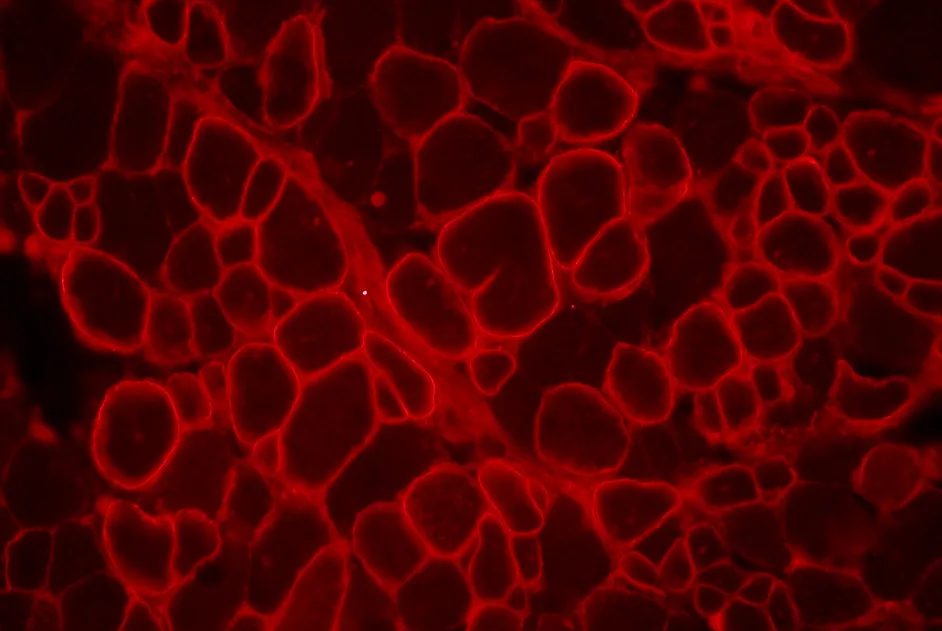

Myasthénie auto-immune : l'essai du tacrolimus

Le tacrolimus est bien toléré dans la myasthénie auto-immune mais il ne permet pas de réduire les doses de prednisolone.